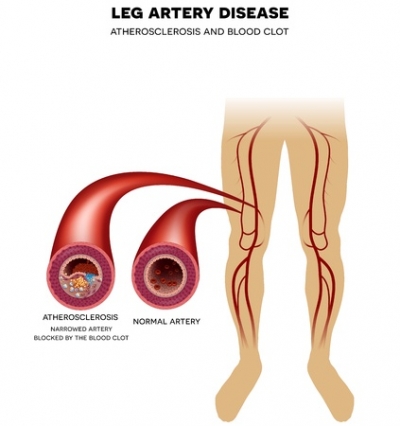

February is National Heart Month and here at Superior Foot & Ankle Center we want patients to understand the vital connection between heart and podiatric health. High blood pressure, or hypertension, is a major contributing factor to heart disease. Hypertension can lead to peripheral artery disease and other circulation problems which can have a significant impact on your feet. Poor circulation, particularly in patients with diabetes can lead to sores and ulcers forming on your feet and increase the risk of amputation. Here are some other facts about hypertension:

If you have not been diagnosed with hypertension but you are experiencing cramping in your feet or changes in feet’s skin color or temperature, make an appointment at our Long Beach office by calling: to see one of our podiatrists, Dr. Victoria M. Foley or Dr. Constance Ornelas. These may be early warning signs of high blood pressure or another condition that the foot doctor will want to evaluate.